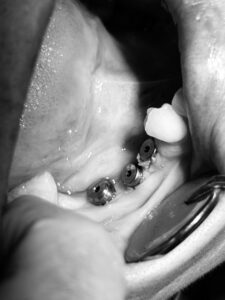

implantes dentales cali

La colocación de implantes dentales es un procedimiento quirúrgico que se realiza en consultorio bajo estrictos protocolos clínicos.

3️⃣ Cirugía de colocación

Todo el procedimiento es realizado por la Dra. Sara Restrepo, garantizando precisión y seguridad.